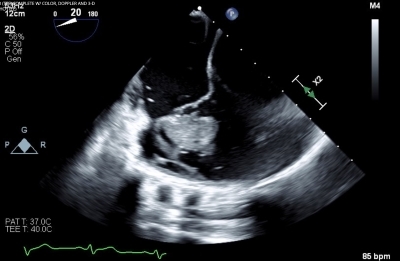

A recently incarcerated 32-year-old man presented with subacute hemoptysis, dyspnea, and night sweats. He had a history of unexplained penile ulcers. His exam was notable for multiple tattoos and a systolic murmur. Chest CTA revealed a 4.6 cm x 2.5 cm right ventricular mass, multiple pulmonary nodules, and bilateral pulmonary emboli. Transesophageal echocardiogram identified a large irregularly bordered mass attached to the anterior tricuspid valve leaflet and right ventricular free wall. Cardiac MRI confirmed a lobulated mass within the right ventricle and an additional 2 cm lesion adjacent to the septum. Multiple sets of blood cultures were negative. Patient had a positive QuantiFERON TB gold and a negative AFB culture, suggesting TB latency. An extensive infectious, hematologic, and rheumatologic workup was otherwise negative. Despite anticoagulation and antibiotics, the mass remained unchanged. The mass was surgically resected, and the tricuspid valve was replaced with a bioprosthetic valve. Histopathology demonstrated an exuberant inflammatory response with organizing granulation tissue from a non-neoplastic process such as organizing hematoma. Postoperatively, the patient developed worsening hemoptysis, requiring intubation and bronchoscopic removal of large airway clots, and upper extremity deep venous thrombosis. Repeat CTA showed multiple pulmonary artery pseudoaneurysms, raising suspicion for vasculitis.